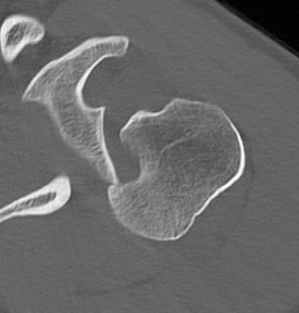

CT scan

Confirms dislocation

Reverse Hill Sachs

Humeral head defect

- caused by impaction of anterior humeral head on posterior glenoid

- intra-articular

- measured as a percentage of the articular surface